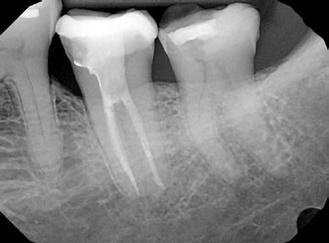

A fogászati technológiák és anyagok területén bekövetkezett hatalmas fejlődés mára a különböző terápiás lehetőségek rendkívül széles palettáját biztosítja a fogorvosok számára. Ugyanakkor, ha kizárólag csak az újdonságok alkalmazásával elérhető izgalmas lehetőségekre fókuszálunk, akkor a kezelések elvégzésének eredeti célja a háttérbe szorulhat. Ezen a ponton fontos kitérnünk a fogászati implantátumok alkalmazására. A szakma sokáig aranystandardként tekintett a károsodott fogak eltávolítására, majd implantátumokkal történő pótlására. Ugyanakkor szakirodalmi adatok igazolják, hogy az endodonciai ellátásban részesült fogak hosszú távú sikeressége 91–97% között mozog. Ezzel ellentétben a periimplantitis és perimucositis előfordulási gyakorisá-

ga Európában 43%, és Észak- és Dél-Amerikában 22% körül mozog. Számtalan tényezőt tudunk megnevezni, amely hozzá tud járulni a periimplantitis kialakulásához, azonban a folyamat kialakulását követően általában csak rövid távon tudunk kedvező eredményeket elérni. Az eddigi tapasztalatok szerint a periimplantáris gyulladás hosszú időn keresztül fennállhat, és gyakran újból ki tud alakulni. Guarnieri és mtsai. vizsgálatuk során megállapították, hogy a krónikus parodontitistől szenvedő pácienseknél alkalmazott megfelelő oki parodontális terápia és az azt követő fenntartó kezelés lehetővé teszi a parodontálisan érintett fogak nagy részének hosszú távú megtartását. Ugyanezen betegcsoportban a saját fogak elvesztéséhez képest sokkal gyakrabban fordul elő a beültetett implantátumok elvesztése. A cikkünkben bemutatásra kerülő eseteket, olyan megfonto-

1. ábra: A 15-ös foggyökér meziális felszíne mellett látható radiolucens elváltozás, illetve a felvételen látható a korábban behelyezett gyökértömés, a parapulpális csap segítségével elhorgonyzott csonkfelépítés és a fogat borító cirkonkorona. –2. ábra: A saggitalis irányú CBCT-metszeten jól megfigyelhető az állcsontgerincet elérő radiolucens elváltozás. – 3. ábra: Az axiális irányú CBCT-metszeten egyértelműen látható a kezeletlen palatinális gyökércsatorna, valamint a radiolucens elváltozás mezio-disztális kiterjedése is jól megítélhető. – 4. ábra: A palatinális gyökércsatorna szelektív endodonciai kezelése során először gyógyszeres zárás került behelyezésre. – 5. ábra: A gyógyszeres zárás során alkalmazott kalcium-hidroxid alapú paszta a szulkuszon keresztül a szájüregbe extrudálódott. – 6. ábra: A gyökértömő anyag a középső és apikális gyökéri harmad határán lévő laterális csatornán keresztül a periapikális térbe extrudálódott. 7. ábra: A kezelések befejezését követően 4 évvel készült röntgenfelvételen jól látható a csontállomány gyógyulása és a fiziológiás gyökérhártyarés újbóli kialakulása. –8. ábra: A peroperatív CBCT-felvétel alapján készített koronális irányú metszeten jól látható a gyökércsúcs körül lévő periapikális felritkulás. – 9. ábra: A kezelések befejezése után 4 évvel készített CBCT-felvételen a gyulladásos lézió teljes megszűnése észlelhető.

10. ábra: A periapikális felvételen egyértelműen megmutatkozik a 46-os és 47-es fogak között kialakult csontos defektus, valamint a gyökereket fedő parodontális rostok károsodása. – 11. ábra: A disztális gyökér amputációját követően a csonthiány kiterjedése látszólag tovább növekedett. – 12. ábra: A 22 évvel később készített kontrollfelvételen jól megfigyelhető a csontos defektus telődése, valamint új kortikális csontállomány kialakulása.

landó – és klinikai körülmények között bizonyítottan működő – példaként akarjuk bemutatni, amelyek iránymutatásként szolgálhatnak a károsodott fogak endodonciai terápiával történő megtartásának lehetőségeivel kapcsolatban.

A CBCT-készülékek endodonciai alkalmazásának talán az az egyik legnagyobb előnye, hogy így olyan anatómiai struktúrák is láthatóvá válnak, amelyeket egyébként nem tudnánk detektálni panoráma, cephalo, vagy periapicalis felvételek segítségével. Mivel a CBCT-felvételek kiértékelése számítógép segítségével történik, így a felvételek vizsgálata során lehetőségünk van az adott területet több nézőpontból és több síkban is megvizsgálni. 2015 októberében egy korábban a rendelőnkben kezelt 55 éves férfi páciens azzal a céllal kereste fel ismét a rendelőnket, hogy másodvéleményt kérjen egy jobb felső kvadránsban található fogával kapcsolatban. Egy másik rendelőben történő vizsgálat során a panaszos fog törését vélelmezték és a fog eltávolítását javasolták, illetve arról is beszámolt, hogy az elmúlt hét során ezen a területen egy puha duzzanat is kialakult. A klinikai vizsgálat során a jobb felső első és második kisőrlő között (14–15) egy fluktuáló duzzanatot észleltünk az áthajlásban. Az 15-ös fog mesialis oldalán 12 mm mély tasakot szondáztunk. A páciens által hozott periapicalis felvételen a 15-ös fog gyökércsúcsának mesialis részén egy nagy kiterjedésű radiolucens elváltozás volt észlelhető (1. ábra). A saggitális síkban vizsgált CBCT-felvételen (Carestream CS 9000, Carestream Dental) a lézió valódi kiterjedése is láthatóvá vált (2. ábra). A megelőző endodonciai kezelések során csupán a bukkális csatorna került detektálásra és gyökértöméssel való ellátásra. Az axiális irányú CBCT-szeleteken egyértelműen látható volt az ellátatlan palatinális gyökércsatorna (3. ábra)

A buccalis csatornába üvegszálas csapot helyeztek, amely a csonkfelépítés elhorgonyzását biztosította. A pácienst arról is tájékoztattuk, hogy egy ferdén behelyezett fém parapulpális csap perforálta a fog koronáját és a csap vége eléri a parodonciumot. A páciens tájékoztatását követően az a döntés született, hogy célszerű lenne a palatinális gyökércsator-

na szelektív endodonciai kezelésének elvégzése. A páciens a javasolt kezelési tervet elfogadta.

Először kalcium-hidroxid alapú ideglenes gyógyszeres zárás került a palatinális csatornába (UltraCal XS, Ultradent Products; 4–5. ábra), amelyet 6 hét után a végleges gyökértömés elkészítése előtt eltávolítottunk. A gyökértömés elkészítése során meleg vertikális kondenzációs technikát alkalmaztunk. Radiológiai felvételen megfigyelhető volt, hogy a gyökértömő anyag egy laterális csatornán keresztül kis mennyiségben a periapicalis térbe extrudálódott (6. ábra). A 4 évvel később készített kontrollfelvételeken a lézió gyógyulása volt megfigyelhető (7–9. ábra). A vizsgálati eredmények és a kezelés kimenetele egyértelműen igazolta, hogy nem gyökérfraktúrával álltunk szemben, tehát a kezdeti diagnózis tévesnek bizonyult. Ez is azt erősíti, hogy korlátozott mennyiségben rendelkezésre álló adatok alapján nem lehet pontos diagnózist felállítani. Manapság szinte elengedhetetlen a CBCT-felvételek endodonciai beavatkozások során történő használata, feltéve, ha ezek elkészítése során az ALARA elv (as low as reasonably achievable) betartásra kerül.

Gyökéramputáció (endo-paro lézió)

Gyökéramputációt főként a furkáció érintett nagyőrlő fogak ellátása során szoktunk alkalmazni. Derks és mtsai. vizsgálatában a gyökéramputált nagyőrlő fogak közel 80%-a 20 évvel a beavatkozás elvégzését követően is megtartott volt. 1998 októberében egy 39 éves férfi páciens a jobb alsó kvadránsban jelentkező ínyérzékenység miatt kereste fel rendelőnket. A klinikai vizsgálat során jobb alsó első és második nagyőrlő fog között (46–47) nagy kiterjedésű csontveszteséget észleltünk. Ettől eltekintve a teljes fogazat parodontális státusza megfelelőnek bizonyult. A jobb alsó kvadránsban végzett szenzibilitás vizsgálat során arra az eredménye jutottunk, hogy a 46-os fog vélelmezhetően elhalt (10. ábra).

A pácienst tájékoztattuk, hogy az endo-paro léziókkal rendelkező fogak alapvetően rossz prognózissal rendelkeznek.

A kezelés hosszú távú sikeressége nagymértékben függ a csontveszteség mértékétől, a megmaradó gyökércsonk hosszától, a gyökerek közti távolságtól, a rezekálni kívánt

gyökér görbületétől, a csontos defektus megszüntetésének sikerességétől, a fogbél állapotától, és a szükséges restauratív és szájhigiénés beavatkozások elvégzésétől.

A páciens beleegyezését követően a 46-os fog disztális gyökere, a disztális gyökér felett lévő koronális rész megőrzése mellett rezekcióra került (11. ábra). A rezekciót követően a referáló orvos a 46. és 47. fogak koronáját Ribbond szalag és kompozit segítségével egymáshoz rögzítette. A sebészi beavatkozást követően 22 évvel készült kontrollfelvételen a lézió csontos telődése, kortikális csontállomány kialakulása, valamint a furkáció körüli csontos regeneráció volt megfigyelhető (12. ábra) A károsodott fogak megtartására szolgáló lehetőségek fejlődésének, valamint az implantátumok behelyezésével kapcsolatos rizikófaktorok jobb megértésének köszönhetően ma már más szemmel vizsgáljuk a fogak eltávolításának szükségességét. A kérdéses prognózissal vagy a kis protetikai értékkel rendelkező fogak eltávolítása előtt mindig érdemes felmérni az ezzel elérhető lehetséges előnyök nagyságát. A kemény- és lágyszöveti pótlás lehetőségeinek fejlődésével, a PRF elérhetőségével, a minimálinvazív sebészeti módszerek és az operációs mikroszkópok elterjedésével, valamint a varróanyagok és varrat technikák egyre kifinomultabbá válásával ma már alaposan el kell gondolkodnunk az előtt, hogy egy fogat egy implantátum behelyezése érdekében eltávolítsunk. Mára sokkal kedvezőbb prognózist és sokkal nagyobb sikerességet tudunk elérni a korábban menthetetlennek gondolt fogak kezelése során.